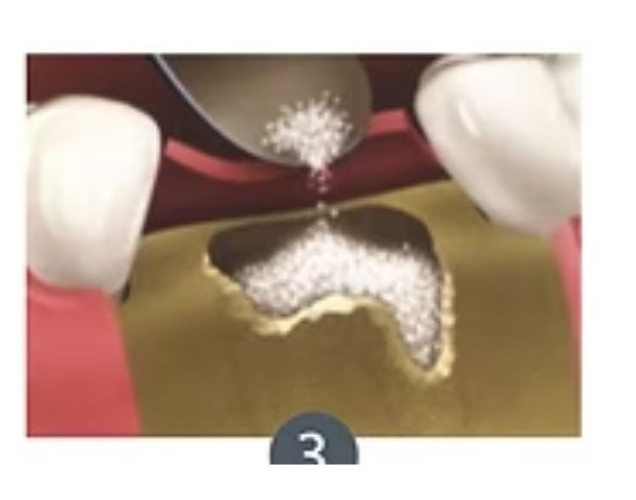

Exodoncia+ Preservación de alvéolo

La exodoncia con preservación del alveolo es un procedimiento dental que combina la extracción de un diente con la protección y preservación del alvéolo dental (la cavidad en el hueso donde estaba el diente) para facilitar futuras restauraciones dentales, como la colocación de implantes dentales.